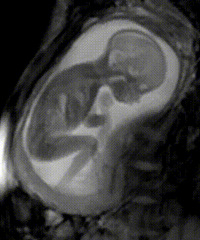

1.胎儿绕颈的原因 ??正常情况下,脐带长度在30—70厘米,一般50厘米左右。若脐带有一定长度时,宝宝在子宫内的动作较大时,脐带可能会被缠绕在脖子上。有时候,过一段时间,脐带会自己松开。

超声影像(四维彩超)的时间要求非常严格医生建议,超声影像(四维彩超)检查的建议时间单胎为孕22—26周,双胎为孕20—22周,孕妈妈们可要记好时间了 ,严格的时间限制是有原因的。错过时间的话就不能做了!为什么如此严格呢?